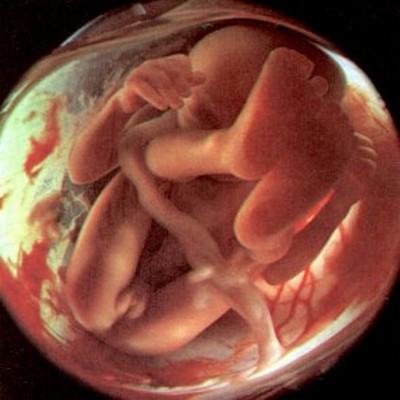

Этапы беременности: иллюстрации и развитие

Раздел: Лаборатория идей